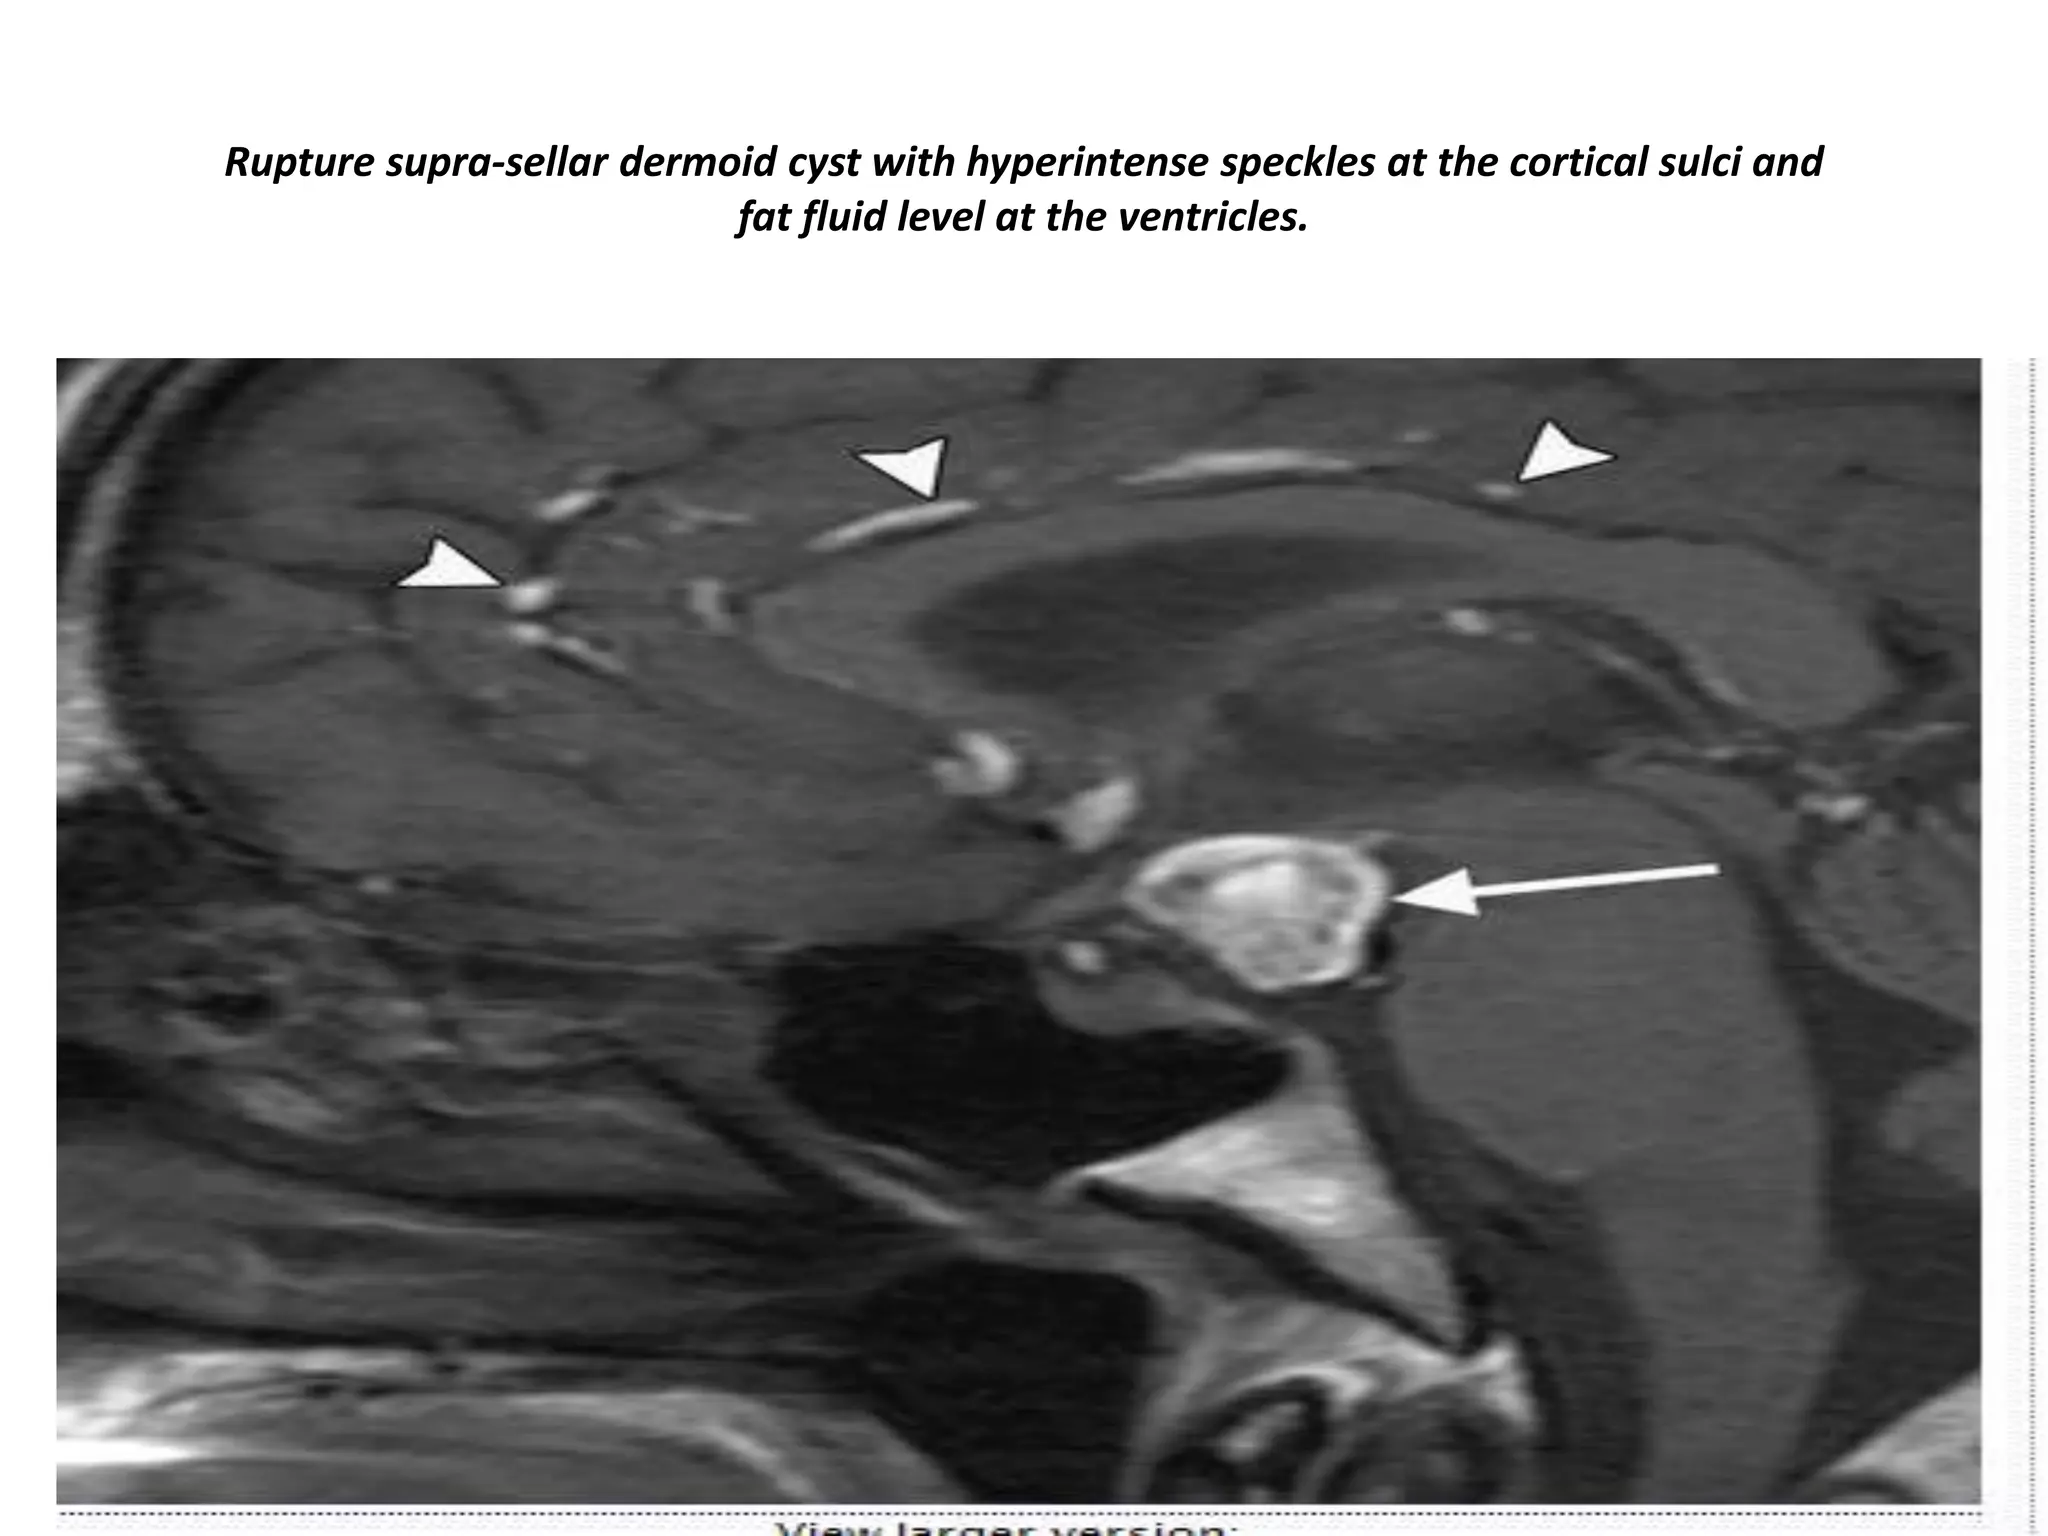

Rupture supra-sellar dermoid cyst with hyperintense speckles at the cortical sulci and

fat fluid level at the ventricles.